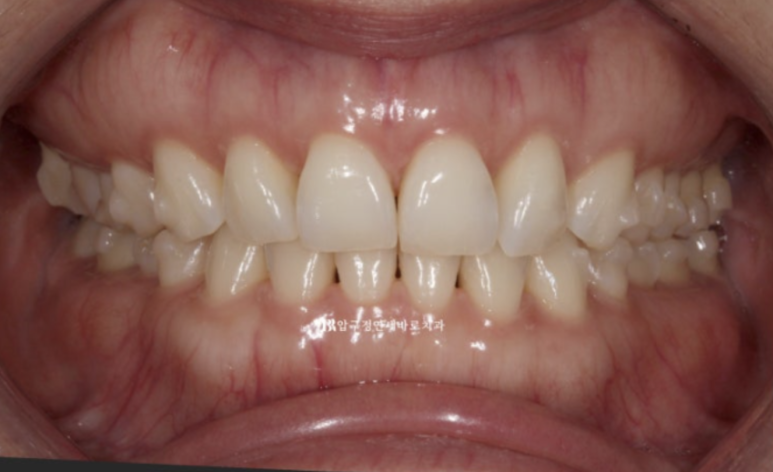

23년 7월부터 23년 12월까지 약 5개월에 걸쳐서 1차세트 장치 14개를 다 착용한 후 모습입니다

23.12

가위교합과 벌어졌던 공간은 이미 해결이 되엇습니다.

중심선도 잘 맞습니다.

블랙 트라이앵글과 치아 사이 미세공간 마무리를 위해 추가적인 제작에 들어갑니다.

가위교합은 1차 세트에서 완전히 개선이 되었기에 미니스크류는 추가장치 제작을 하기로 한 날 제거했습니다.